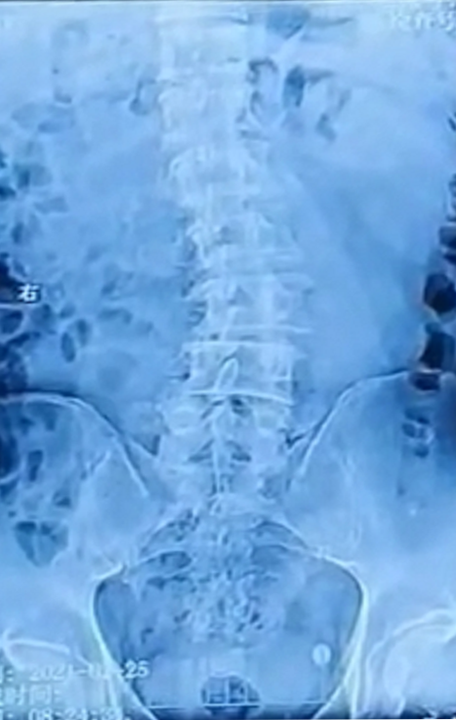

下腰椎侧弯

腰椎的下腰区出现一个向左侧的侧凸,腰椎2/3,3/4,4/5都有不同程度的退

腰椎全场侧位,术前给予精密设计.